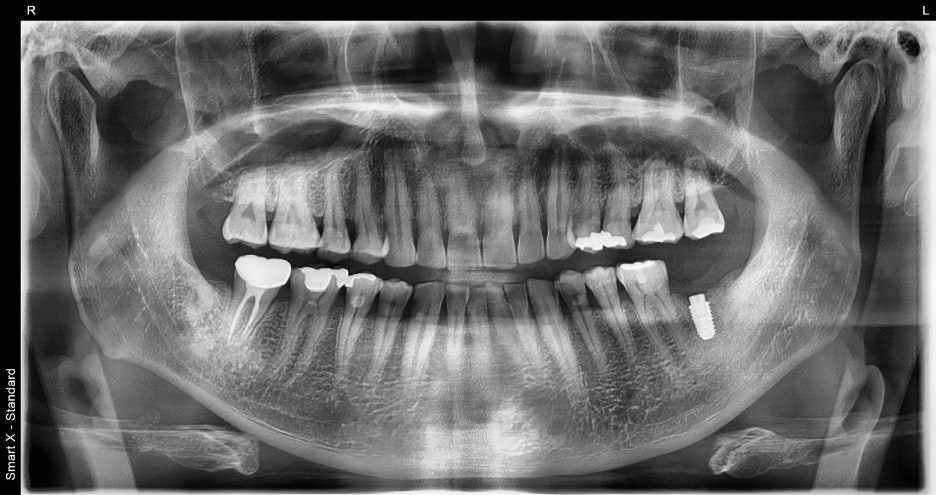

According to the panoramic X-ray,

the lower left molar had already been extracted,

and the surrounding bone condition was good,

so implant placement was confirmed to be possible without additional bone grafting.